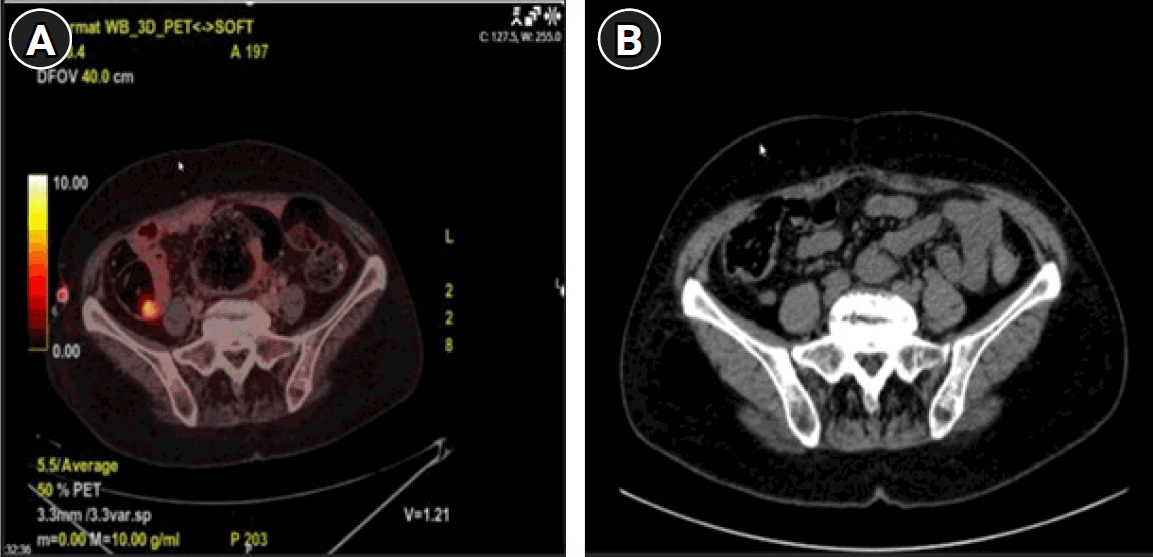

A comprehensive paraneoplastic and autoimmune encephalitis panel was sent from both serum and CSF (Table 1). Serum testing was positive for anti-Yo antibodies, whereas CSF testing was negative. Based on the clinical findings and the positive anti-Yo result, a diagnosis of PCD was established. The patient received 1,000 mg of intravenous methylprednisolone daily for 10 days, followed by oral prednisolone 60 mg/day, with a planned tapering schedule to discontinue the steroid within 2 months. Whole-body contrast-enhanced CT performed as part of the malignancy screening revealed no evidence of cancer (Fig. 1). Following treatment, the patient's symptoms improved considerably. Agitation, personality changes, insomnia, and disinhibition demonstrated marked improvement, whereas ataxia exhibited a comparatively lesser degree of recovery. The patient was subsequently discharged. One week later, the patient presented to the emergency department with severe abdominal pain. Clinical evaluation revealed urinary retention (glob vesical), and 5,000 mL of urine was drained following Foley catheter insertion. The patient was re-hospitalized, and cranial, cervical, thoracic, and lumbar MRI were performed, all of which were unremarkable. During follow-up, the patient developed fecal incontinence. A subsequent whole-body positron emission tomography-CT scan demonstrated abnormal metabolic activity in the appendiceal region (Fig. 1), raising suspicion for an underlying neoplastic process. Colonoscopy revealed an ulcerated lesion at the appendiceal orifice. Histopathological evaluation of the biopsy specimen reported a tubulovillous adenoma with high-grade dysplasia. The patient subsequently underwent surgical resection, with a cecal base resection being performed. Intraoperative frozen section analysis confirmed clear surgical margins. Gross examination of the resected appendix revealed a 2×1.5×1-cm polypoid tumor located in the proximal portion of the appendix, approximately 1 cm from the surgical margin. Histologically, the tumor was identified as a well-differentiated adenocarcinoma arising from a tubulovillous adenoma. The lesion demonstrated invasion into the mucosa and submucosa, without extension into the muscularis propria, corresponding to pT1 staging. No lymphovascular invasion was observed. Immunohistochemical analysis for mismatch repair (MMR) proteins showed preserved nuclear expression of MLH1, MSH2, MSH6, and PMS2, indicating a microsatellite stable phenotype. The final diagnosis was consistent with early-stage (T1N0) appendiceal adenocarcinoma with negative surgical margins. On postoperative day 2, the Foley catheter was removed. There was no recurrence of urinary retention, and the previously observed fecal incontinence resolved completely. Corticosteroid therapy was tapered and discontinued. The patient's behavioral changes, insomnia, and agitation showed near-complete resolution. Ataxia improved significantly, although not entirely. The patient was subsequently followed without any immunosuppressive therapy. At the 2.5-year follow-up, no evidence of tumor recurrence was detected. The patient continued to exhibit only mild residual ataxia and balance disturbance, with complete resolution of all other symptoms.

Fig. 1.

(A) Positron emission tomography-computed tomography demonstrated focal fluorodeoxyglucose uptake in the appendiceal region. (B) Abdominal computed tomography revealed no evidence of an appendiceal lesion.